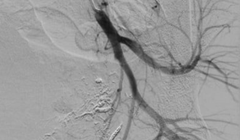

Hình ảnh sau nút mạch quanh động mạch trực tràng của bệnh nhân (Ảnh - BVCC)

90 phút “cân não” cứu sống sản phụ bị tổn thương động mạch trực tràng lần đầu tiên xuất hiện ở VN

VietTimes – Các bác sĩ ở Trung tâm Điện quang, Bệnh viện Bạch Mai, vừa cứu sống sản phụ bị tổn thương động mạch trực tràng hiếm gặp lần đầu tiên xuất hiện tại Việt Nam.